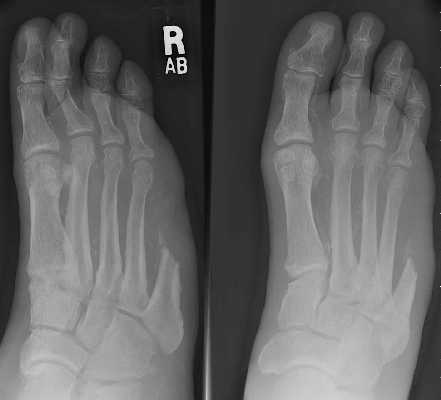

Occasionally because of infection with or without ischemia,

particularly in the diabetic foot and occasionally following trauma, removal of one or

more of the central rays, either partially or completely is indicated.